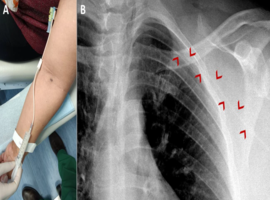

Citation: Couto MC, Tavares NT, Barbosa M. Totally Implanted Venous Catheter: What Can Go Wrong? Clin Image Case Rep J. 2025; 7(5): 569.